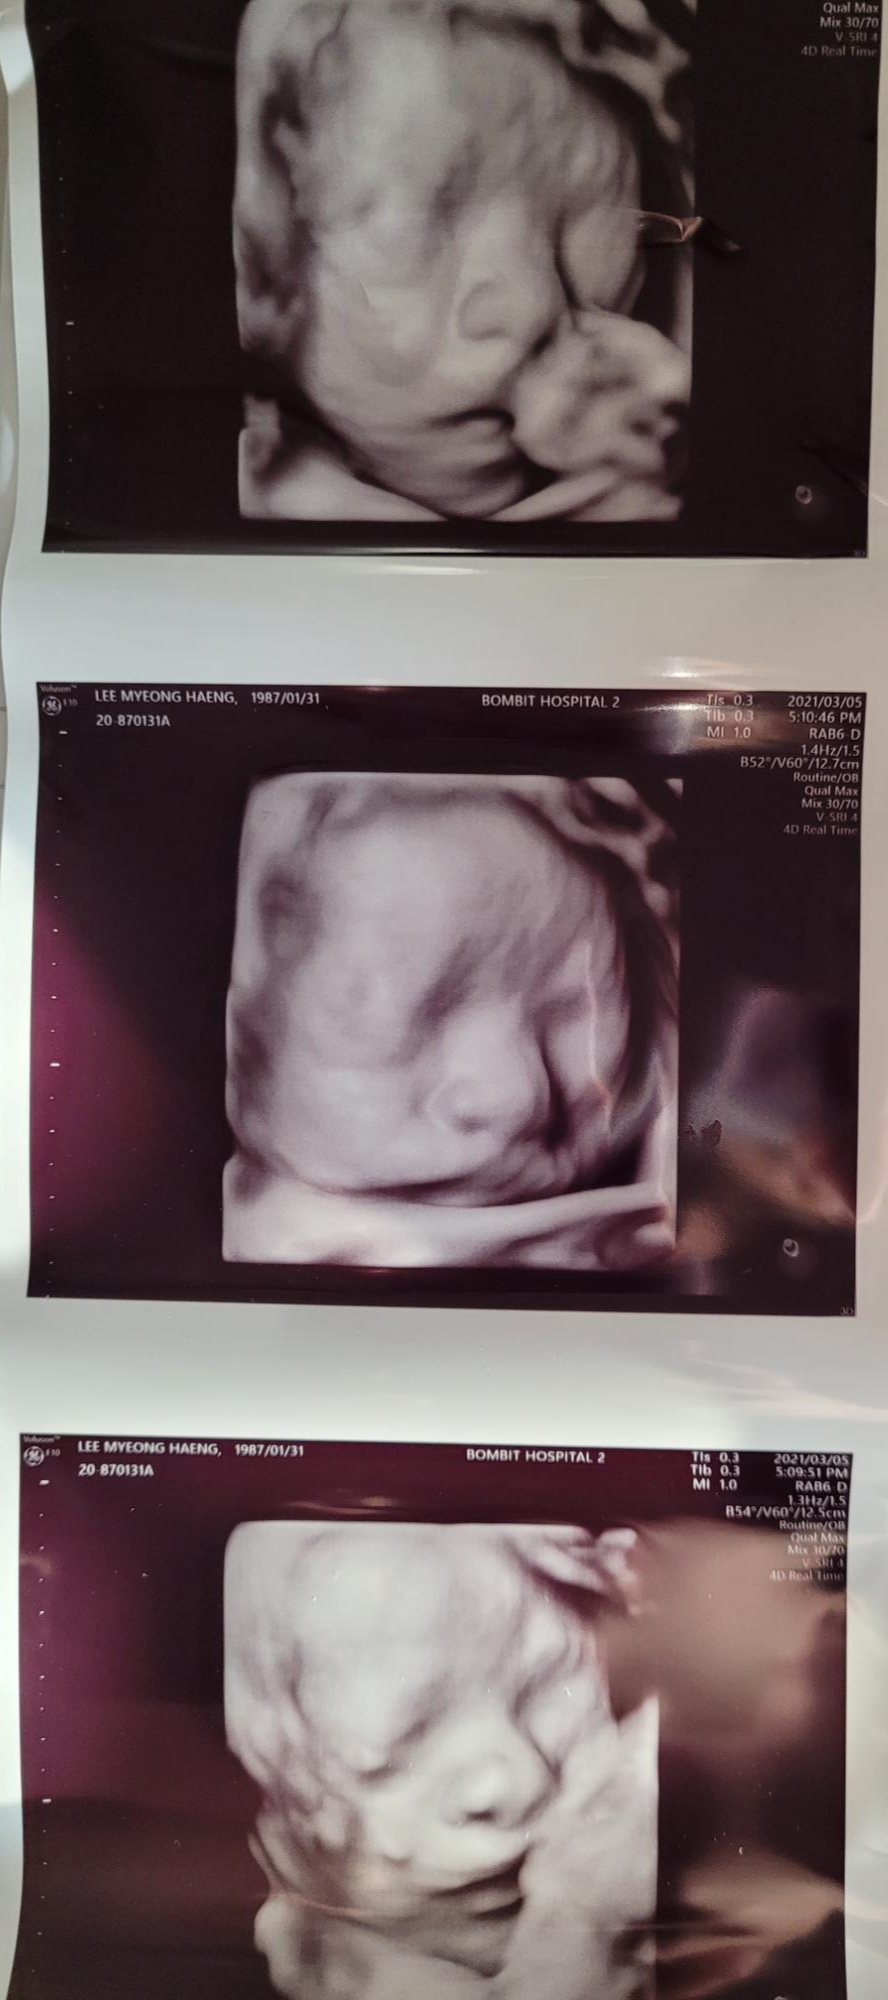

임신 27주 입체초음파 후기

24주에 정기검진을 하고, 27~28주쯤 입체초음파를 보고싶으면 예약을 하면된다고 하셨어요.

27주~28주쯤이 제일 아기가 잘 보인다고 해요.

너무 커도 잘 안보인다고해서 27주로 예약했고요.

소요시간은 아기가 얼마나 얼굴을 잘 보여주느냐에 따라 다르지만 보통 10분~20분 내외인것같아요.

초반에는 뒤돌아있어서 흔들흔들하고 옆으로 누웠더리 얼굴을 보여주더라구요

선생님이 어떻게 잘 찍어주시느냐에 따라서도 달라지는거같아요

순간포착을 잘해야되더라구요^^

영상으로 보면 더 신기했어요.

태반으로 가려져있는 얼굴을 슥슥 편집해서 잘 보이게해주시더라구요.